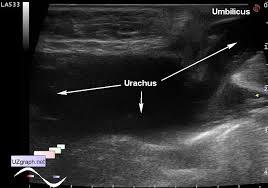

Urachal fistula

Urachal fistula

What is a urichal fistula?

Urachus doesn't close and belly button leaks urin

what is a Urachus?

a fibrous cord that extends from the umbilicus to the bladder.